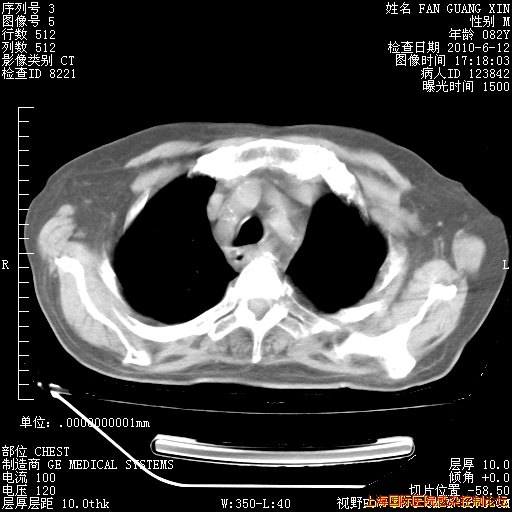

补发6月12日肺部CT肺窗

6月12日肺窗

6月12日纵膈窗

整整相隔30天的肺部CT好像有所好转啊。甲强龙减量第3天,需要观察体温。